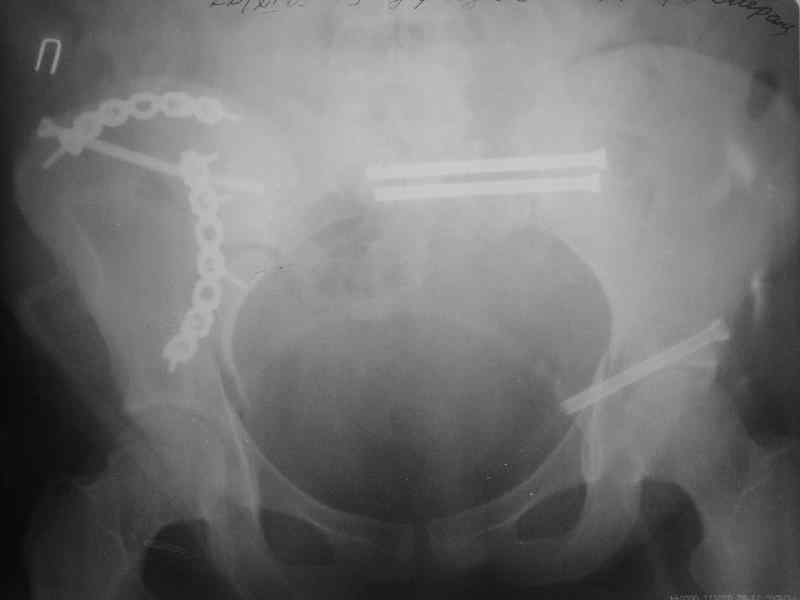

Молодая девушка 19 лет, травма 1 год назад, тогда же прооперирована.

В приложении снимки при поступлении и послеоперационные год назад.

Могу сказать одно: миграция винтов и нестабильность синтеза левого подвздошно-крестцовогоо сочленения очевидна.

Забыл добавить, что ИХМО показан реостеосинтез более длинными винтами, с более широкой резьбой, с фиксацией за правое подвдошно-крестцовое сочленение.